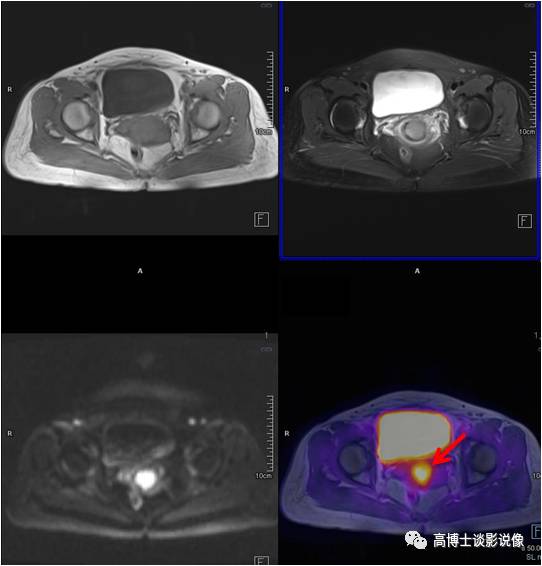

子宫肌瘤

年轻女性,无明显不适。子宫后壁肌层可见一椭圆形异常信号灶,长径约3.3cm, FDG无代谢,诊断为子宫肌瘤。

点评

子宫肌瘤是女性生殖系统中最常见的一种良性肿瘤。子宫肌瘤较小或者不位于黏膜下的,一般无症状,明显增大后会压迫膀胱等邻近脏器,或者造成月经量增多,甚至腹痛等不适。常规检查B超可以解决问题,PET/MR可以帮助鉴别子宫病变良恶性。治疗因人而异。

卵巢囊肿

年轻女性,无明显不适。左侧附件区见一长径约5.0cm椭圆形囊性信号灶,边界清楚,FDG未见明显摄取,考虑为卵巢囊肿。

PET/MR检查常常会发现卵巢囊性病变,多数为生理性囊肿(滤泡或黄体囊肿),均与女性内分泌功能相关,随着体内激素水平的变化而变化,因此发现此种卵巢囊肿后不必过分紧张,大于3cm者,建议B超定期随访复查。